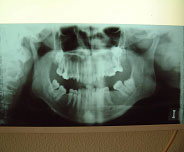

La angulación de los cóndilos en el plano axial (12), el insuficiente desarrollo de los cóndilos (Hipoplasia) (13, 14), son factores que favorecen la aparición de patología y más aun si se añaden sobrecargas funcionales. Un cóndilo hipoplásico (Fig. 1) nos obligará a proteger más las articulaciones durante la realización de las higienes dentales, para no sobrecargarlas y favorecer así la aparición de patología.

Fig. 1 Hipoplasia Condilar

Fig.2 Ausencia de sectores posteriores Este estudio, nos ayuda a mantener el concepto de que el aumento de la carga articular por pérdida del soporte posterior (ausencia de molares) (Fig. 2), aumenta los signos y síntomas en los desórdenes craneomandibulares, incluyendo cambios estructurales óseos.

La mordida abierta anterior esquelética (Fig. 3), las sobremordidas horizontales de más de 6mm. (Fig. 4), una distancia mayor de 4mm. desde relación céntrica a máxima intercuspidación, mordida cruzada unilateral (Fig. 5 y 6) y ausencia de sectores posteriores de 5 ó más piezas, han sido los factores oclusales que se han asociado con grupos de diagnóstico específicos en disfunción de la ATM.